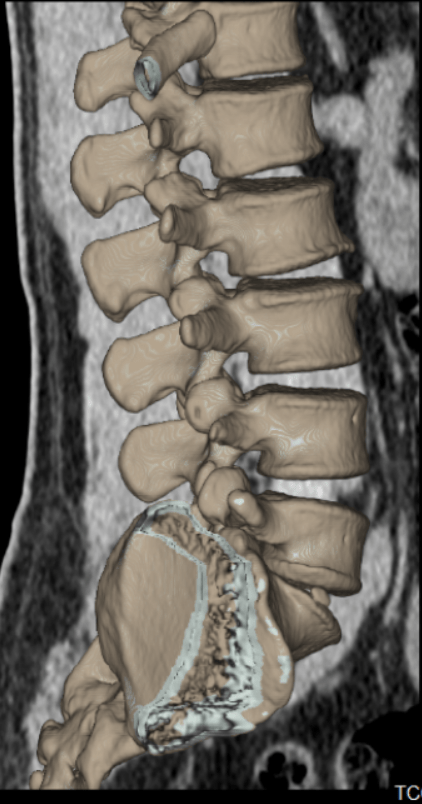

A tomografia computadorizada de coluna é um exame de imagem de alta qualidade e nitidez, que proporciona a identificação de várias patologias que atingem a área da coluna vertebral, como espondilose (artrose na coluna), estenose vertebral (aperto na coluna), espondilolistese (deslizamentos vertebrais), traumas e outros. A ressonância apresenta sensibilidade maior para detectar hérnias. Contudo, nos casos de trauma, a tomografia computadorizada é um excelente método de imagem.